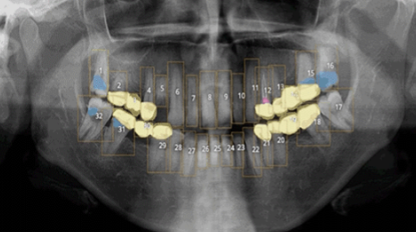

VELMENI for Dentists® 2D

VELMENI is as easy to use as it is powerful. Scan 2D radiographs to increase detection accuracy by 30%. FDA cleared for 2D Panoramic, Bitewing and Periapical X-Rays.